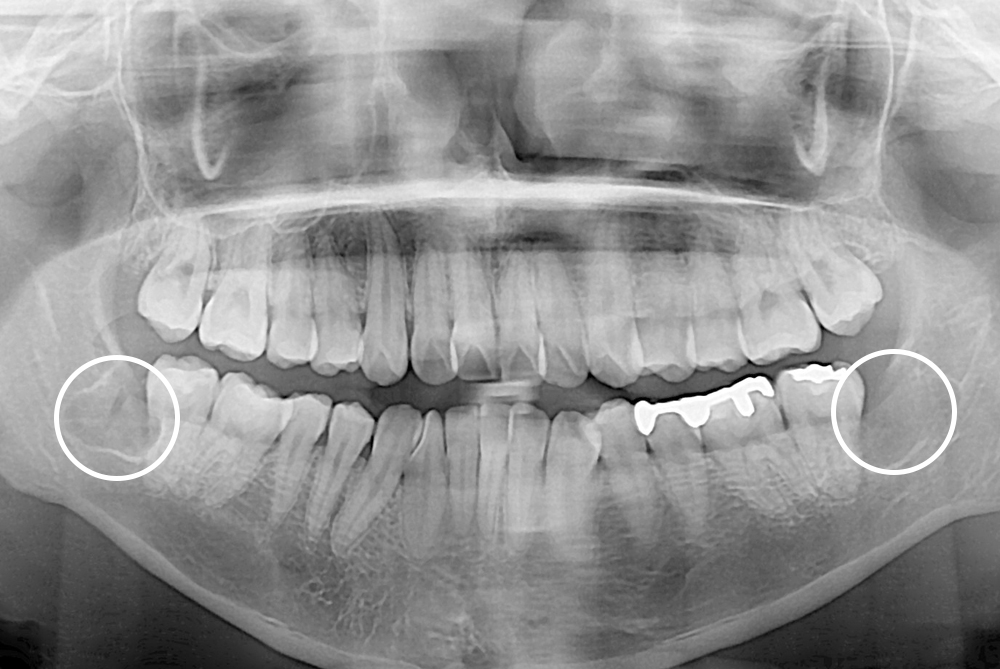

[사랑니] 매복 사랑니 발치

치료후 : 2019-05-02

세종치과는 구강악안면외과학 박사이신 원장님이 발치하는 치과입니다.